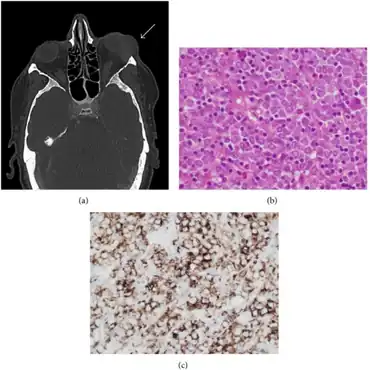

a) CT shows left periorbital myeloid sarcoma b) blast infiltration by myeloid sarcoma c) positive immunohistochemical staining for CD34 in myeloid sarcoma

Definitive diagnosis of a chloroma usually requires a biopsy of the lesion in question. Historically, even with a tissue biopsy, pathologic misdiagnosis was an important problem, particularly in patients without a clear pre-existing diagnosis of acute myeloid leukemia to guide the pathologist. In one published series on chloroma, the authors stated that 47% of the patients were initially misdiagnosed, most often as having a malignant lymphoma.[8]

However, with advances in diagnostic techniques, the diagnosis of chloromas can be made more reliable. Traweek et al. described the use of a commercially available panel of monoclonal antibodies, against myeloperoxidase, CD68, CD43, and CD20, to accurately diagnose chloroma via immunohistochemistry and differentiate it from lymphoma.[9] Nowadays, immunohistochemical staining using monoclonal antibodies against CD33 and CD117 would be the mainstay of diagnosis. The increasingly refined use of flow cytometry has also facilitated more accurate diagnosis of these lesions.